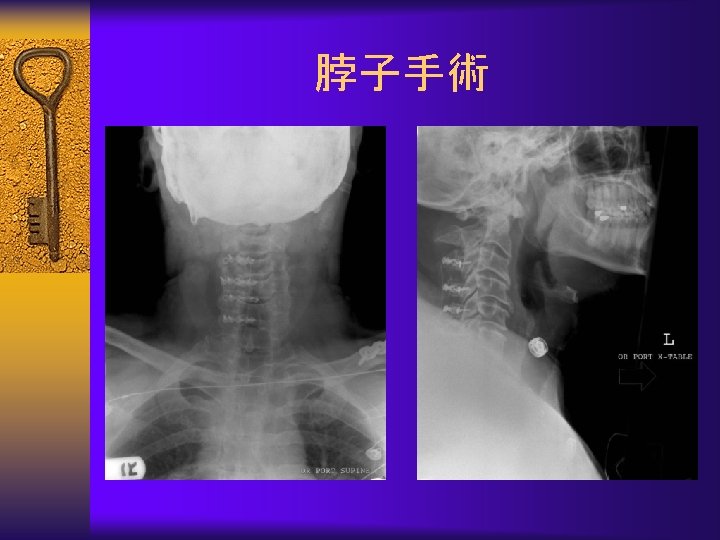

Surgical Treatment-Fusion 融 合 ¨ Instability – Spondylolisthesis – Scoliosis – Severe disc degeneration

Surgical Treatment-Fusion(融 合)